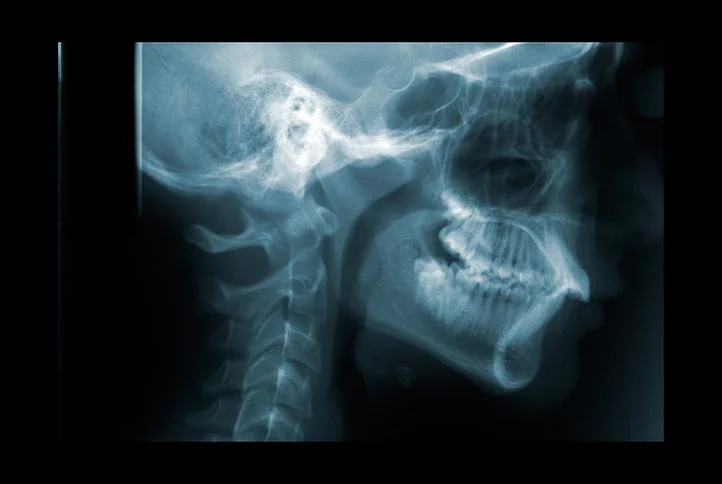

Warning signs of head and neck cancers

Most of us are familiar with knowing the warning signs of breast or skin cancers. But many of us may not be as well-educated on recognizing the signs and symptoms of cancers of the head and neck. They could be as innocent as a small lump below the jaw line that doesn’t go away or hoarseness to your voice you attribute to allergies. Each year, approximately 48,000 Americans are diagnosed with a head or neck cancer. These tumors account for up to 5 percent of all cancers in the U.S.